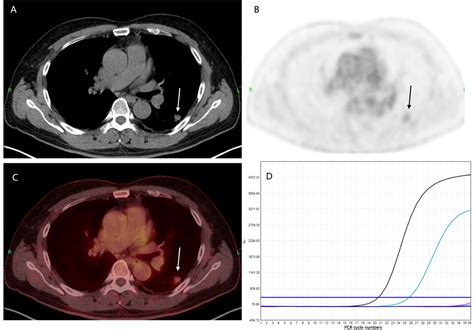

PET-CT scans are a powerful diagnostic tool that combines the strengths of both PET and CT scans. PET scans use a radioactive tracer to highlight areas of high metabolic activity, which is often indicative of cancer cells. CT scans, on the other hand, provide detailed anatomical images of the body. When combined, PET-CT scans offer a comprehensive view of both the structure and function of the body's tissues, making them invaluable in the diagnosis and staging of Pet Ct Lung Cancer.

PET-CT scans involve the injection of a radioactive tracer, typically a form of glucose, into the patient's bloodstream. Cancer cells, which have a higher metabolic rate, absorb more of the tracer than normal cells. The PET scanner then detects the radiation emitted by the tracer, creating images that highlight areas of high metabolic activity. Simultaneously, the CT scanner takes detailed images of the body's structures, which are then fused with the PET images to provide a precise location of the cancerous cells.

• Accurate Staging: The detailed images provided by PET-CT scans help in accurately staging the cancer, which is crucial for determining the appropriate treatment plan. Staging involves assessing the size and extent of the tumor, as well as whether it has spread to other parts of the body.

Interpreting the results of a PET-CT scan involves a detailed analysis by a radiologist. The images are reviewed to identify areas of high metabolic activity, which may indicate the presence of cancer. The results are then shared with the patient's healthcare team, who will discuss the findings and develop a treatment plan. It is important to note that while PET-CT scans are highly accurate, they are not foolproof. False positives and false negatives can occur, and additional tests may be needed to confirm the diagnosis.